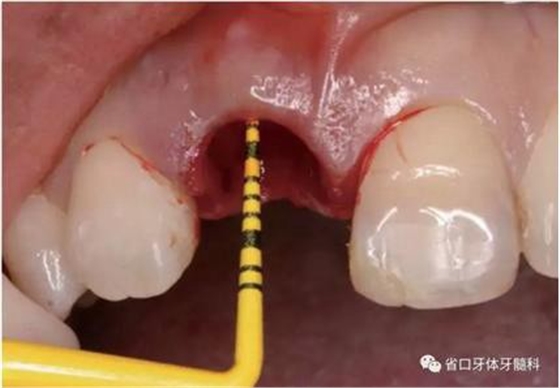

圖9 探測唇側(cè)骨壁完整

圖10 唇側(cè)骨壁完整

(1)微創(chuàng)拔牙及即刻種植:術(shù)前拍攝口內(nèi)照及實(shí)施牙周基礎(chǔ)治療。常 規(guī)消毒鋪巾阿替卡因局麻下微創(chuàng)拔除上頜右側(cè)中切牙,搔刮拔牙窩及根尖肉 芽組織。探測牙槽骨唇側(cè)骨壁及鄰面牙槽嵴完整,牙齦無撕裂。不翻瓣下于上頜右側(cè)中切牙缺隙近遠(yuǎn)中中點(diǎn)的腭側(cè)牙槽骨及根方定位,按照逐級預(yù)備的原則,緊貼牙槽窩腭側(cè)骨壁制備種植窩洞,植入Zimer®3.7mm×13mm TSV種植體1顆,植入扭矩>35N·cm,以O(shè)sstell測量種植體的ISQ值為68。 種植體平臺位于唇側(cè)齦緣中點(diǎn)下3mm,與唇側(cè)骨壁內(nèi)側(cè)面形成的跳躍間 隙約2mm,置入Bio-Oss®細(xì)顆粒骨粉0.25g,上愈合基臺關(guān)閉創(chuàng)口。術(shù)后 CBCT檢查顯示:種植體利用牙槽窩根方骨質(zhì)固位,緊貼牙槽窩腭側(cè)骨壁, 其唇側(cè)面與牙槽窩唇側(cè)骨壁的內(nèi)側(cè)面所形成的跳躍間隙(約2mm)可見顆 粒狀顯影物充填。牙槽窩的唇側(cè)骨壁及唇側(cè)倒凹無缺損穿孔。